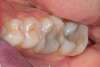

SECTEURS POSTÉRIEURS MAXILLAIRES ET MANDIBULAIRES

Remplacement de composites et/ou d'amalgames (plombages) défectueux par une résine composite esthétique restaurant la morphologie initiale des dents.